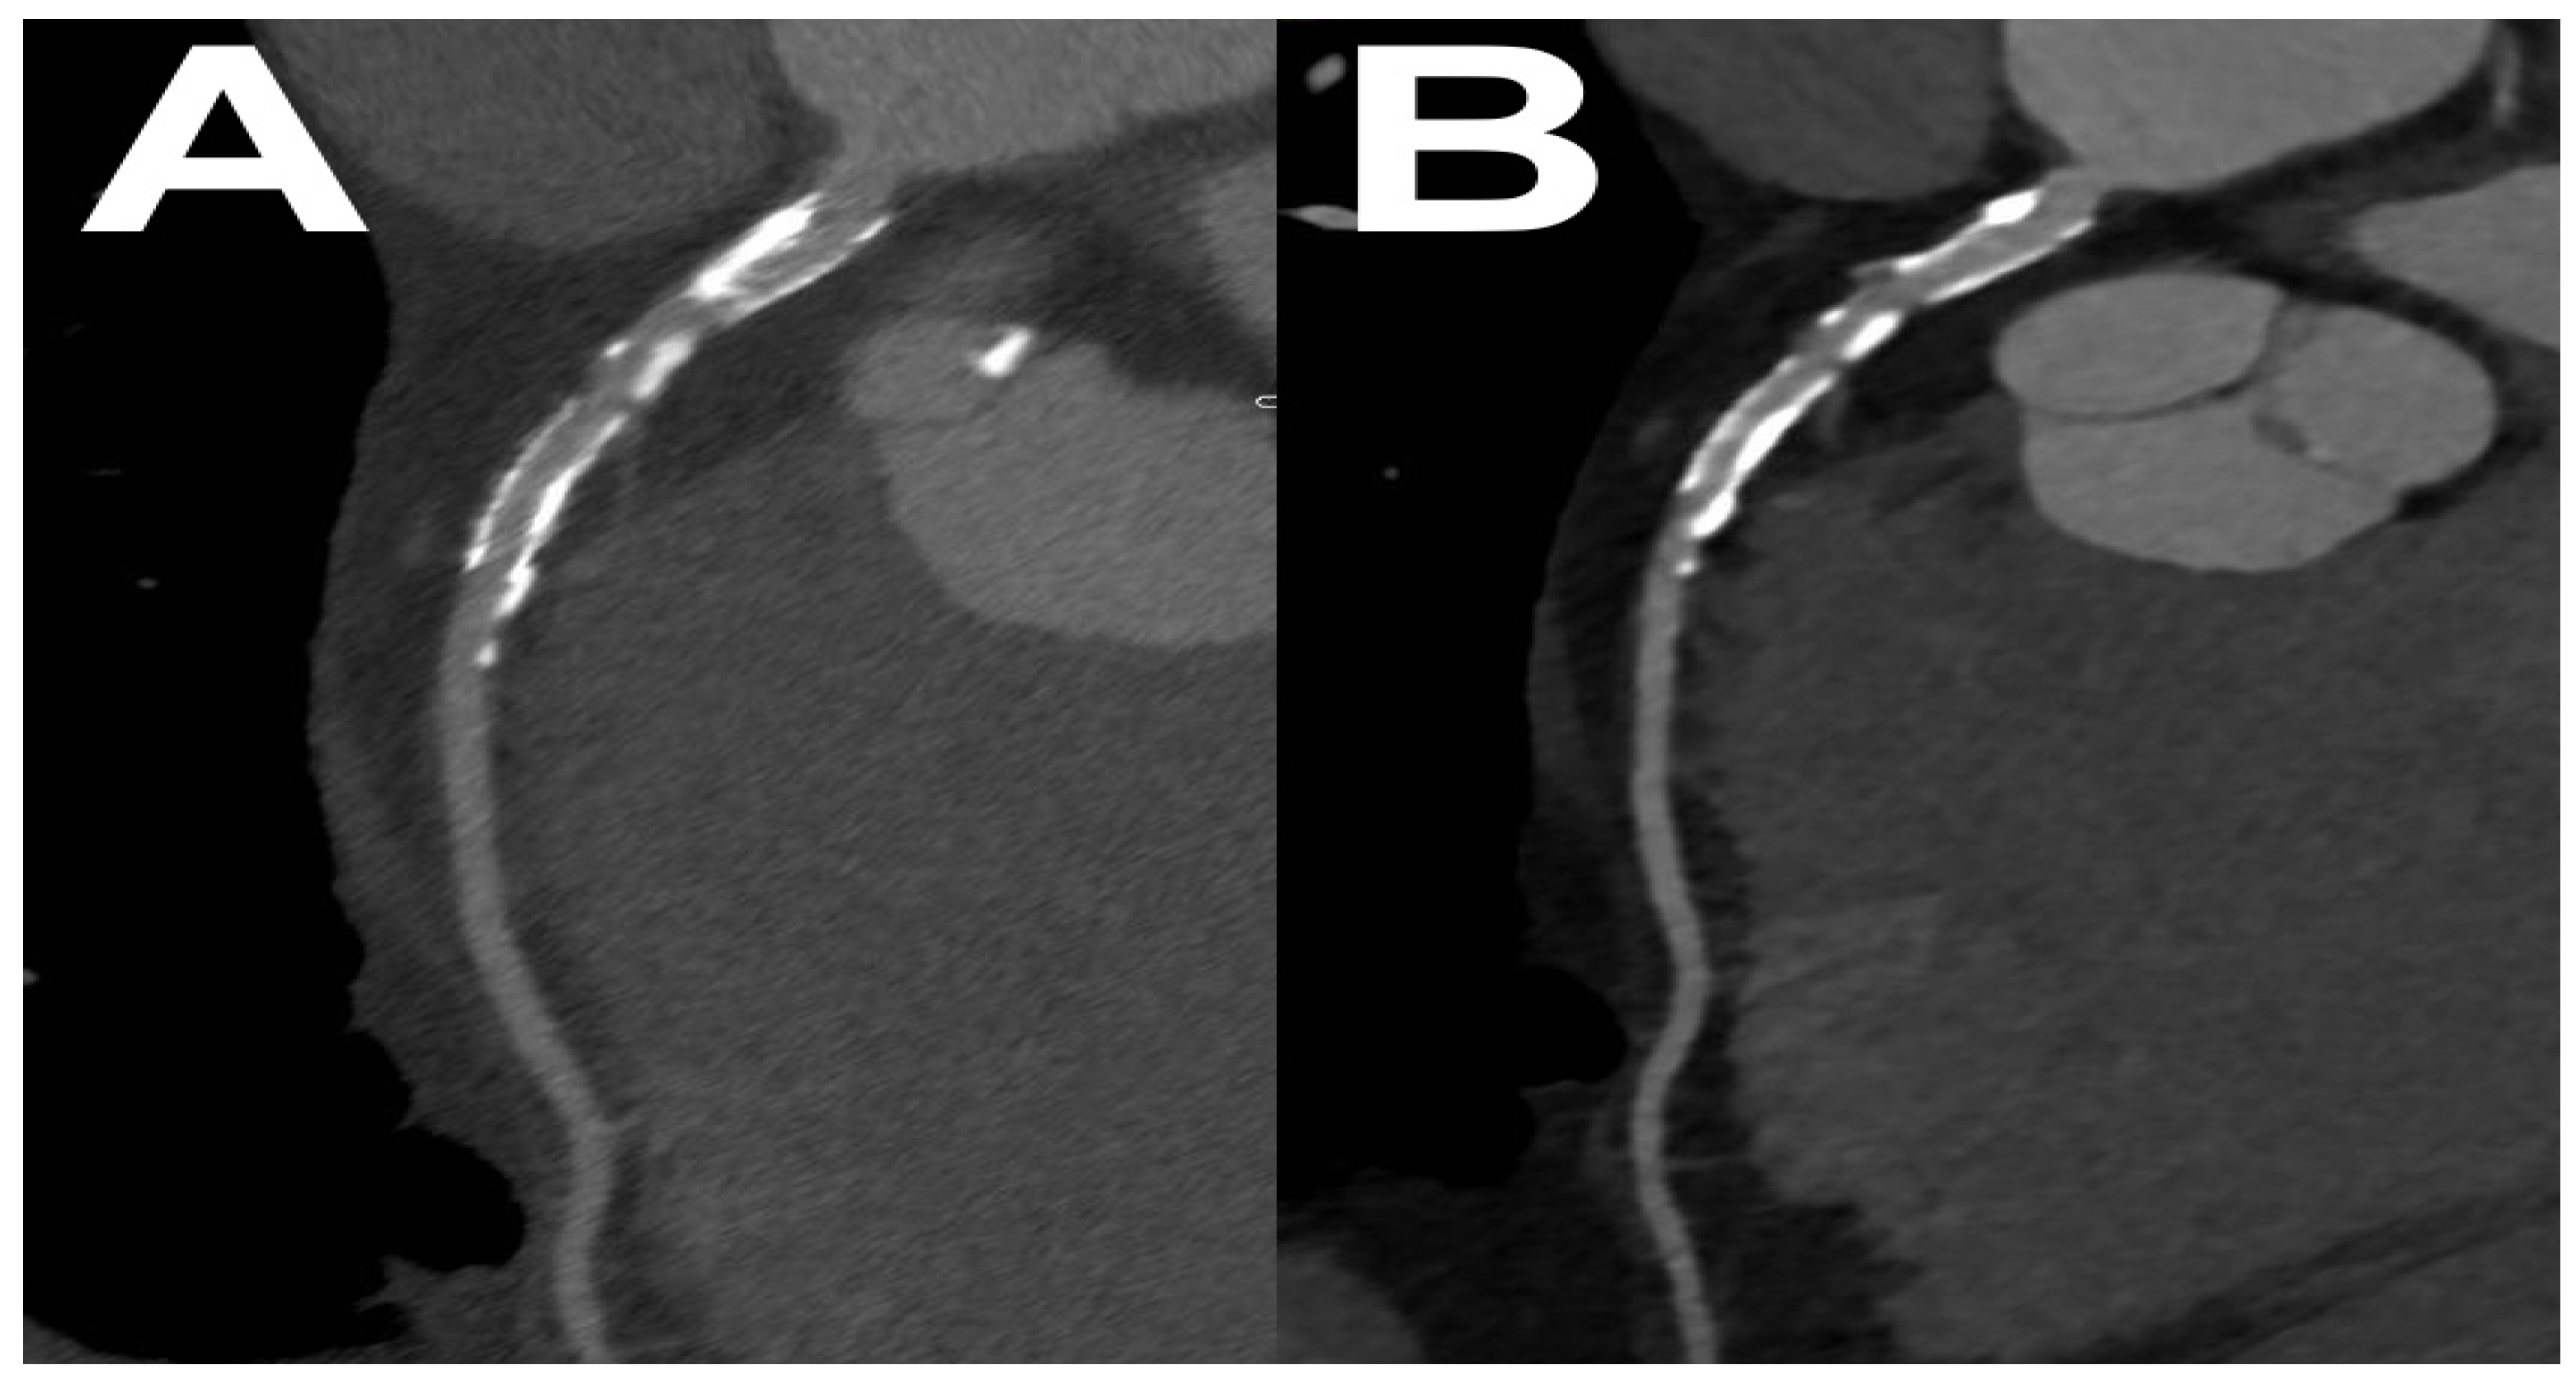

- Kazimierczak, W.; Nowak, E.; Kazimierczak, N.; Jankowski, T.; Jankowska, A.; Serafin, Z. The Value of Metal Artifact Reduction and Iterative Algorithms in Dual Energy CT Angiography in Patients after Complex Endovascular Aortic Aneurysm Repair. Heliyon 2023, 9, e20700. [Google Scholar] [CrossRef]